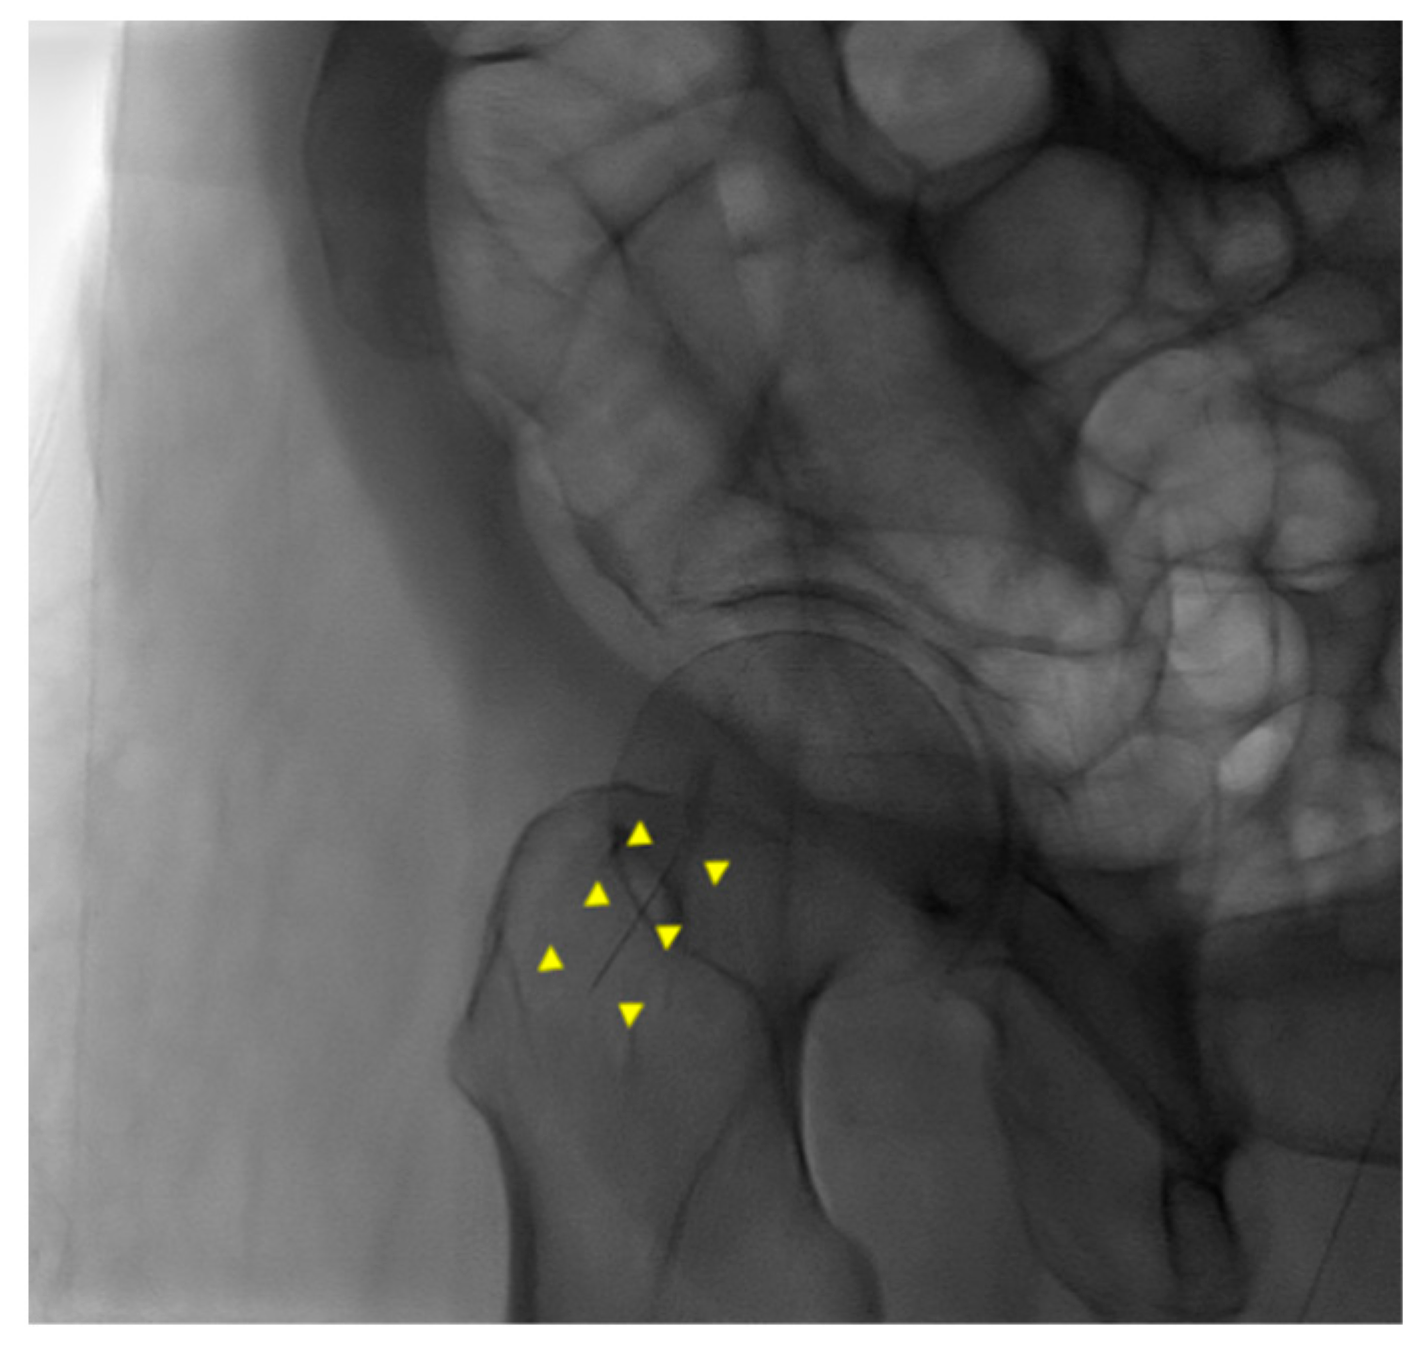

An 87-year-old female patient came to the emergency department with increased bilateral pleural effusion with pneumonia, and she was admitted for treatment. She had been bedridden with comorbidities, including old cerebral infarction, hypertension, and had left femur neck fracture with endoprosthesis for 4 weeks before admission. Her body mass index was 26.67 kg/m2. She was generally edematous. We drained pleural effusion, diagnosed as parapneumonic effusion, and administered intravenous antibiotics for the treatment of pneumonia with parapneumonic effusion. During hospitalization, her conditions were wax and wane, with aspiration pneumonia. On day 37 of hospitalization, her blood pressure was consistently low despite the use of a vasopressor. For arterial blood gas analysis (ABGA) to monitor the patient’s state of acidosis, we repeatedly performed puncture of the right femoral artery instead of the radial or dorsal artery. We used a 25 gauge and 16 mm length needle for femoral arterial puncture. After blood extraction, while drawing the syringe out of a femoral artery, the needle was disconnected from the syringe. The needle remained in the groin of the patient, and its location was not identified through portable ultrasonography. Radiography of the pelvic bone showed the needle fragment in the right groin (Figure 1). Fluoroscopic radiography revealed the exact location of the needle fragment (Figure 2). A surgical incision was performed to obtain the embedded needle in the soft tissue of the groin, without penetrating the femoral artery. The needle fragment was removed (Figure 3) completely without complications. The needle was bent as it was pulled out with mosquito forceps (Figure 3).

Figure 2. Fluoroscopic radiography of pelvic bone. A needle fragment showed in the right groin (yellow triangles).

Figure 3. A piece of needle fragment retrieved from the groin and the used syringe. The bent needle while pulling it out with mosquito forceps.